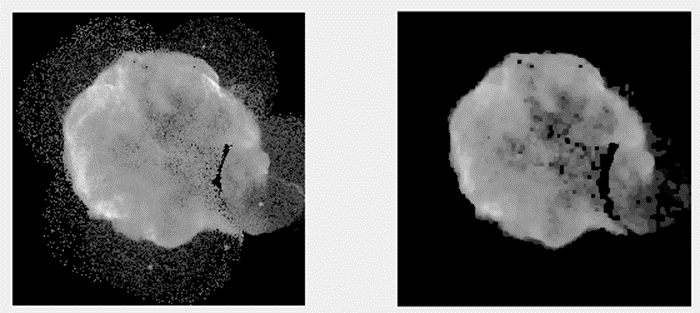

对于题目二中的图片来说,在开始形态学处理之前需要先消除黑噪声。根据上文所述,在进行灰度图象形态学处理时会采用腐蚀与膨胀的操作序列以去除黑噪声;接着为了去除非 wanted noise(白噪声),需对图片进行反转并再次应用相反的操作以除去白噪声;随后采用闭合处理过程(即先进行膨胀再进行腐蚀),从而彻底清除白噪声;最后再次反转图片的灰度等级以恢复正常状态;最终输出的图片已成功消除黑噪声和白噪声的影响

对于实验4中的肺部图像,在结果显示部分需通过反复测试确定最优的DISK圆盘形态。当半径过小时不适合使用,在测试过程中会发现当半径过大时同样不合适。

(5)最初阶段,在图像中进行腐蚀与膨胀操作以去除黑色背景区域内的灰黑色噪声像素。随后对图像进行反向处理,并通过闭操作进一步去除白色噪声。经过上述处理后得到的结果是:背景变为纯黑且已去除所有残留噪声。如图5所示对比可知,在保留主要细节信息的同时去除了大部分不希望存在的噪声

在进行肺部图像填充时,我们需要尝试不同大小的结构元素作为参数。在选择较小的结构元素(如半径3)时,在某些情况下无法完全填充肺部区域。使用较大的结构元素(如半径10)可能导致两个原本分离的肺部区域被错误地连接在一起。适当选择较大的结构元素(如半径7)则能够有效地达到目标:不仅能够正确地填充肺部内部区域,并且不同的肺部区域不会被连通。